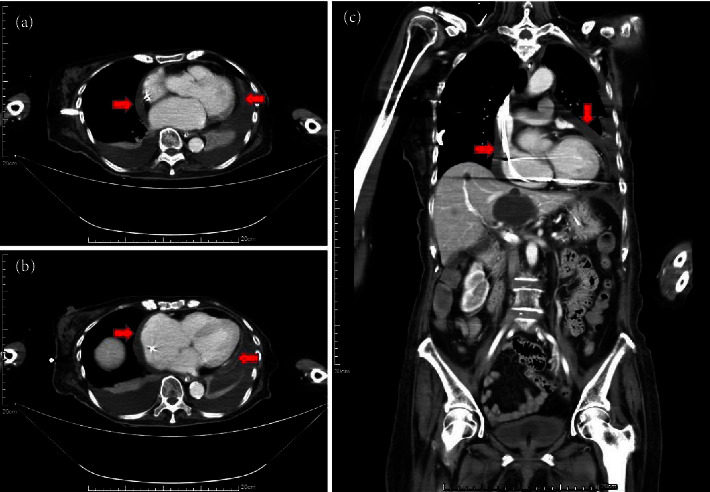

The occurrence of sporadic rickettsial infections has been consistently undervalued and overlooked, primarily owing to a limited emphasis on routine examinations for rickettsioses in clinical practice. At present, the immunofluorescence assay is the prevailing diagnostic method for suspected rickettsioses that enables the detection of specific antibodies against rickettsia in human serum. Herein, we present an exceptional instance of rickettsial infection that was characterized by a rare manifestation of extensive pericardial effusion leading to dyspnea and cardiac tamponade. A diagnosis of chronic fibrosing pericarditis was established based on pericardium tissue obtained through pericardiotomy, and a conclusive metagenomic next-generation sequencing test confirmed the presence of Rickettsia felis infection. The cat flea, scientifically known as Ctenocephalides felis, is the predominant carrier of R. felis. An escalating incidence of human R. felis infections has raised concerns, particularly in light of the burgeoning population of domesticated animals in many contemporary societies.